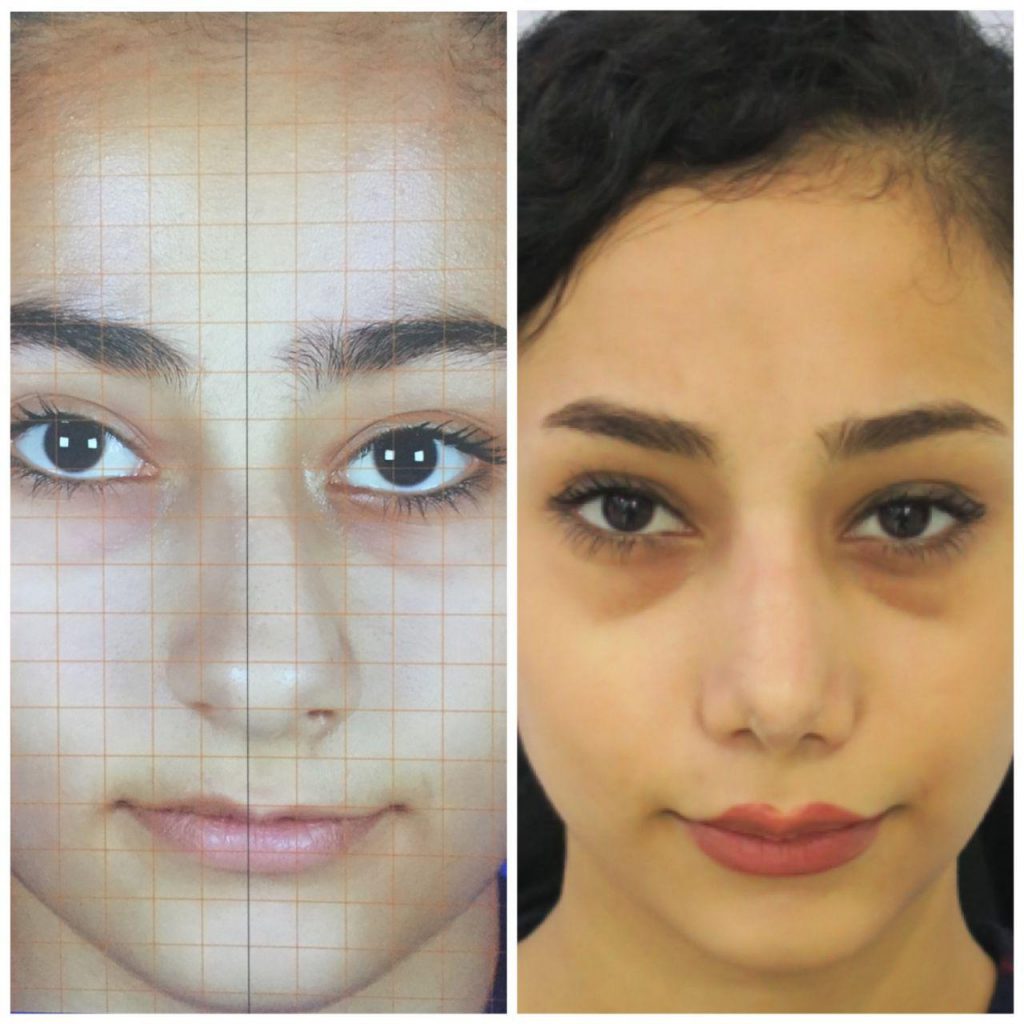

دکتر عیسی عبدی در رشت

دکتر عیسی عبدی در رشت

– متخصص جراحی فک , پلاستیک صورت و بینی

دکتر عیسی عبدی در رشت

جراحی فک , پلاستیک , صورت وبینی

جراحی ترمیمی و زیبایی فک و صورت و جمجمه و گردن

صورتشان از روبهرو و پهلو تقارن ندارد.